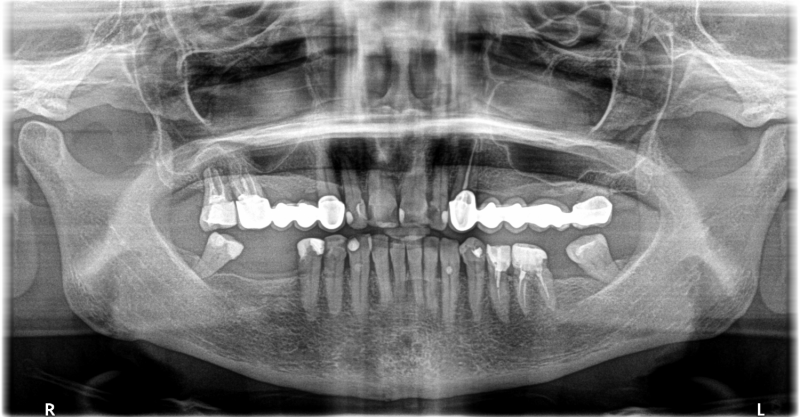

Wykonana praca protetyczna:

- licówki pełnoceramiczne na zębach górnych przednich

- korony pełnoceramiczne na zębach własnych w łuku górnym i dolnym

- korony na implanatch